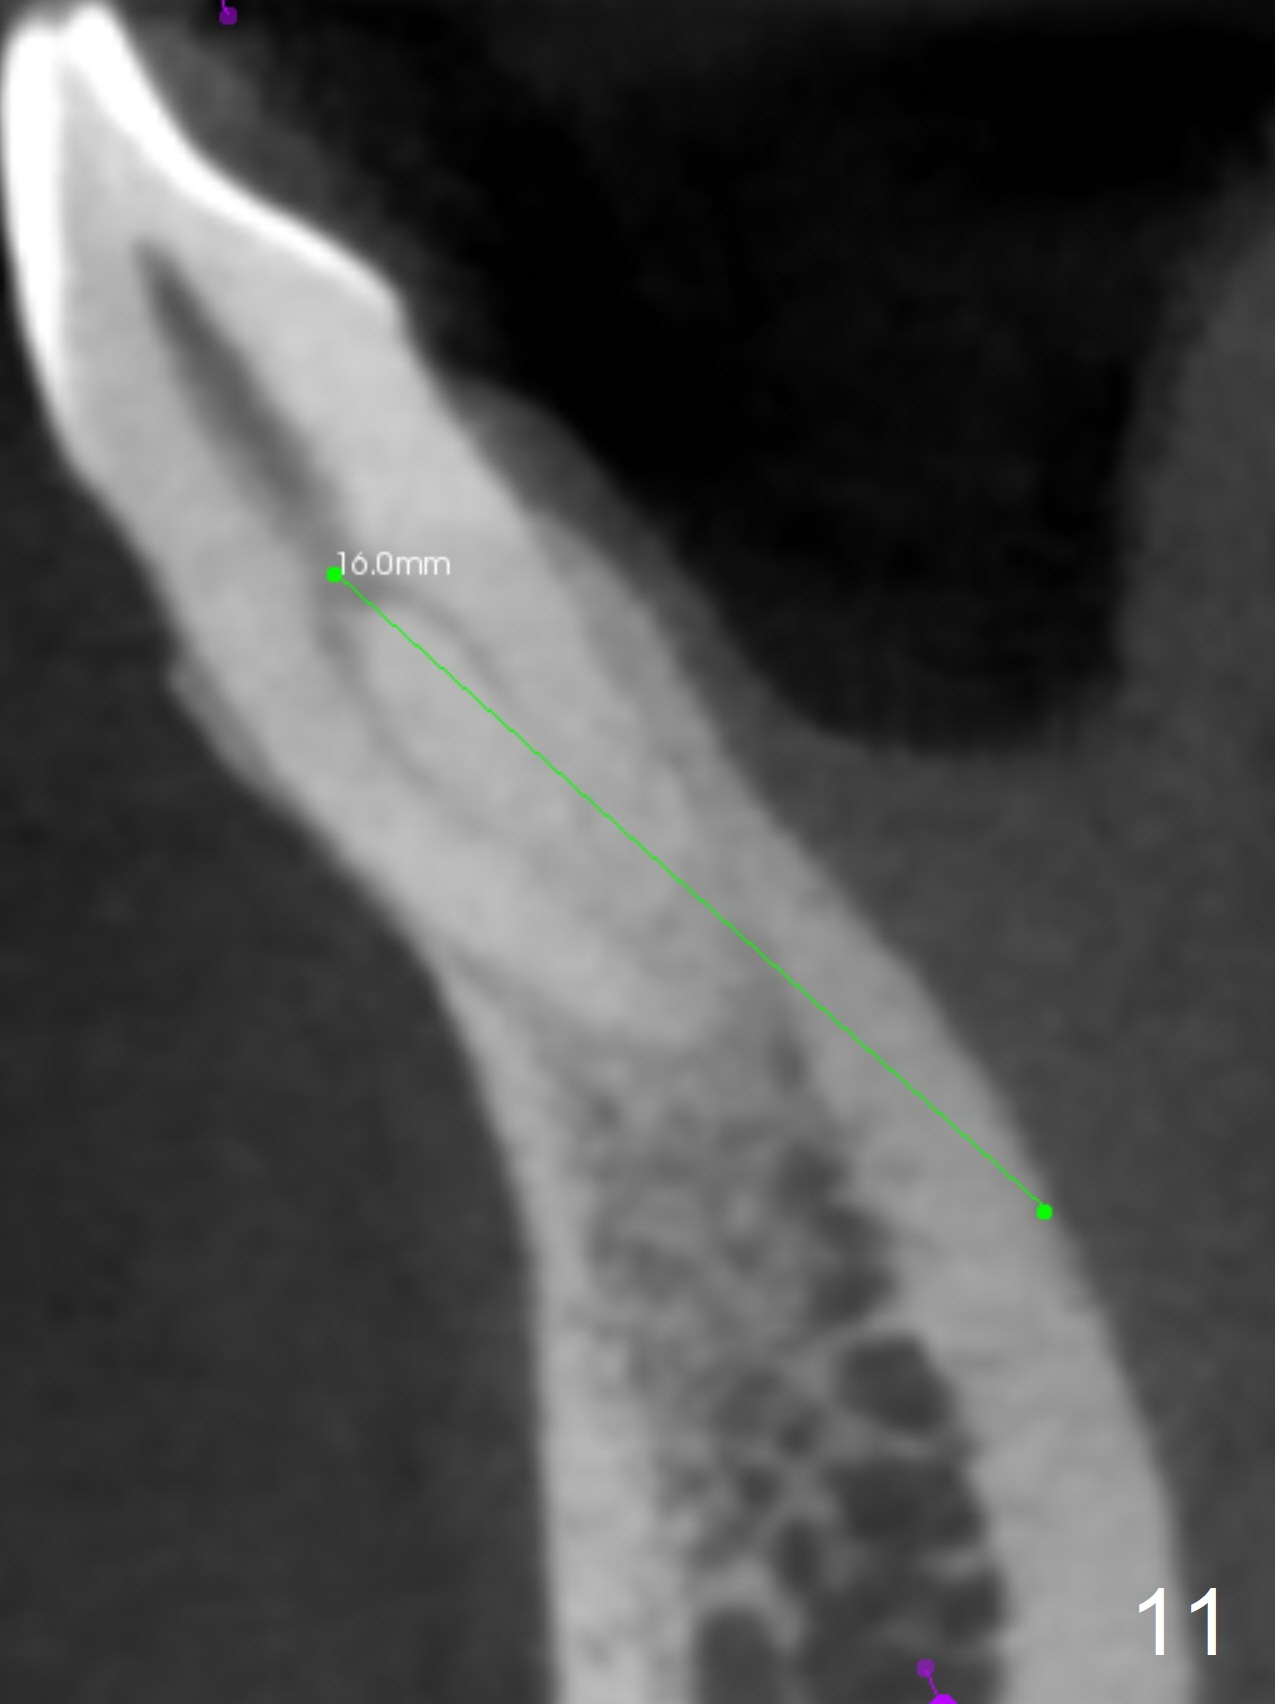

In fact the apex of the lateral incisor is also in the center of the alveolus (Fig.9 *). Osteotomy established in the lingual slope for a long distance (Fig.10,11) will perforate the lingual plate. The correct method of osteotomy is to set up in the middle of the socket and along the long axis of the alveolus with 2 fingers holding the alveolus (Fig.12 (2 circles)). The problem for this case is to use the lower RPD as a guide. With the RPD in place, the tactile sensation is lost.

After change in abutment at #27 and abutment height adjustment at #26 and 27 (Fig.13), splinted provisional is fabricated with clearance from the RPD (Fig.14) and seal of the sockets (Fig.15). Acute submandibular and submental cellulitis develops with sublingual purulent discharge 1 month 10 days postop (Fig.16). CT confirms lingual plate perforation at both sites (Fig.17,18; red line: original socket). With block anesthesia, removal of these implants causes mild discomfort. With Hydrogen Peroxide and normal saline copious irrigation, pain reduces when anesthesia subsides. Bone graft will be placed at the sites approximately in 2 weeks. In fact the infection is not controlled until 2 weeks later (Fig.19). The clasp has to be covered with acrylic for comfort (Fig.20). The previous implant sites heal 1.5 months post implant removal (Fig.22).